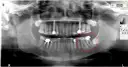

Dorosły człowiek ma zazwyczaj od 28 do 32 zębów stałych. Ta liczba może się różnić w zależności od obecności zębów mądrości, które są ostatnimi zębami pojawiającymi się w jamie ustnej. W typowym pełnym uzębieniu stałym znajduje się 8 siekaczy, 4 kły, 8 zębów przedtrzonowych oraz 12 zębów trzonowych. Zęby mądrości mogą się nie rozwijać u niektórych osób lub wymagać usunięcia z powodu braku miejsca w szczęce.

Standardowa liczba zębów u dorosłych wynosi od 28 do 32. Zwykle, w pełnym uzębieniu, zęby mądrości są uwzględniane w tej liczbie, co może wpływać na całkowity wynik. U niektórych osób zęby mądrości mogą nie rozwijać się wcale, co skutkuje posiadaniem jedynie 28 zębów. W przypadku, gdy zęby mądrości są obecne, ich liczba może wzrosnąć do 32.

W liczbie zębów u dorosłych mogą występować znaczące indywidualne różnice. Genetyka odgrywa kluczową rolę w tym, ile zębów ma dana osoba. Niektórzy ludzie mogą mieć więcej zębów z powodu obecności zębów mądrości, podczas gdy inni mogą ich nie mieć wcale. Dodatkowo, stan zdrowia jamy ustnej, taki jak choroby dziąseł czy wcześniejsze ekstrakcje, również wpływa na ostateczną liczbę zębów. W rezultacie, liczba zębów może się wahać od 28 do 32, a czasami nawet mniej, jeśli występują poważne problemy zdrowotne.